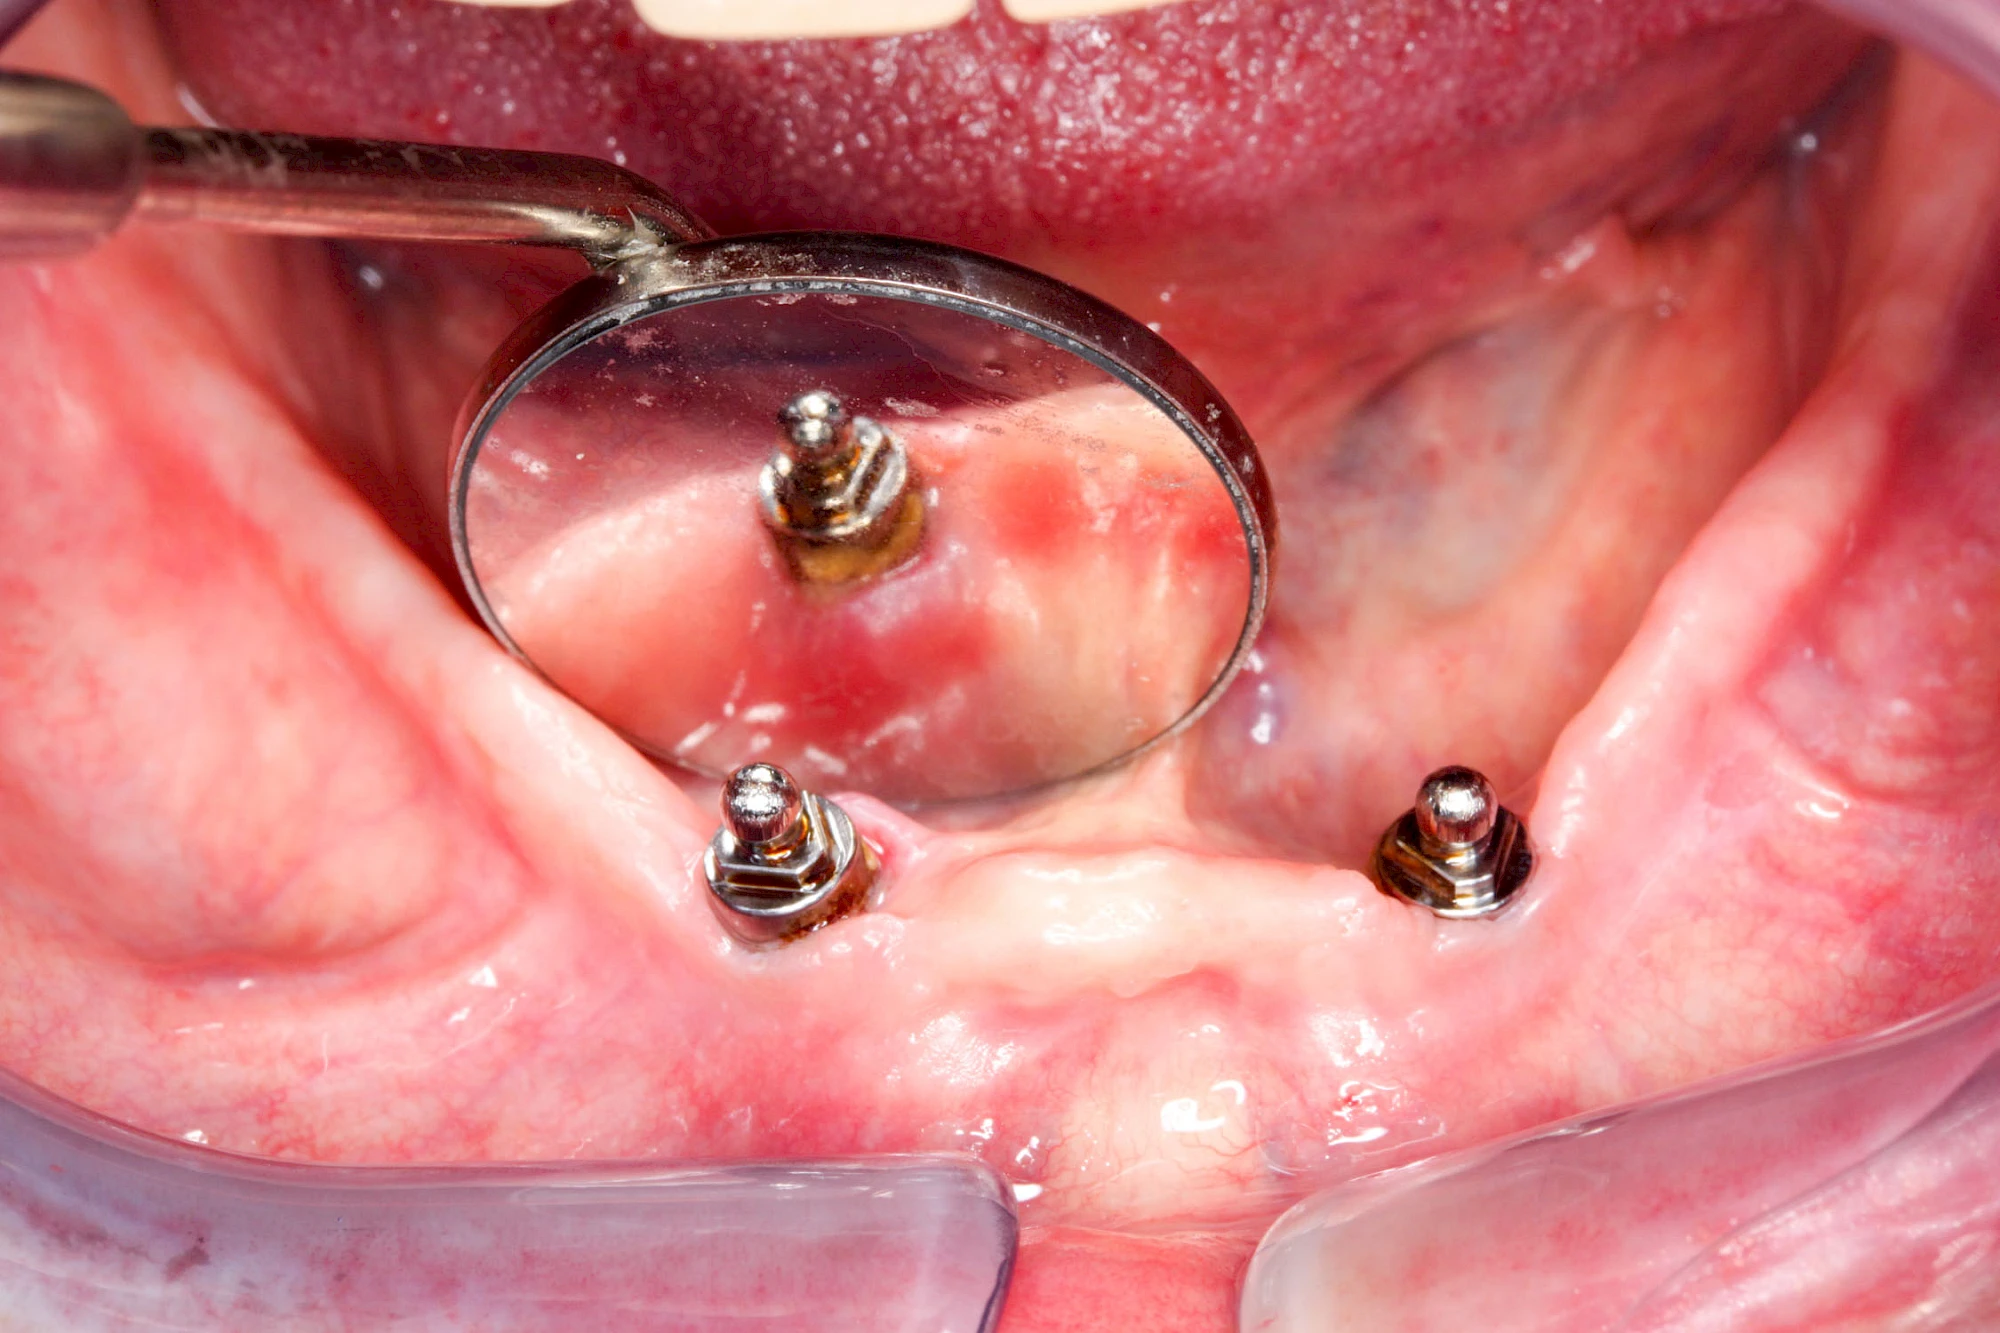

Bei Implantaten – also operativ eingebrachten künstlichen Zahnwurzeln – kann der Körper die Bakterien auch nicht so gut abwehren. Hier spricht man im Fall einer Entzündung von einer Peri-Implantitis, also einer Entzündung um das Implantat herum.